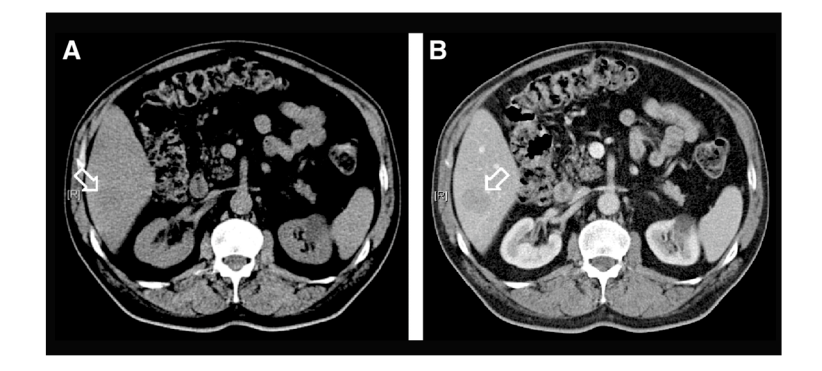

于是,当“对比剂(造影剂)”被用于CT、MR等增强扫描时,医生首次清晰看到了极其微小的病灶;如今也成为早期肿瘤筛查,尤其是精准诊断结节的利器。

增强后的CT图像,可辨别低密度病灶